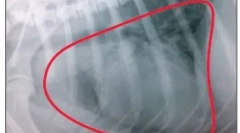

Кісткові пухлини

Пухлини можуть виникати в різних частинах скелетної м`язової системи - кістки, суглобів, кінцівок, що з`єднують тканини.